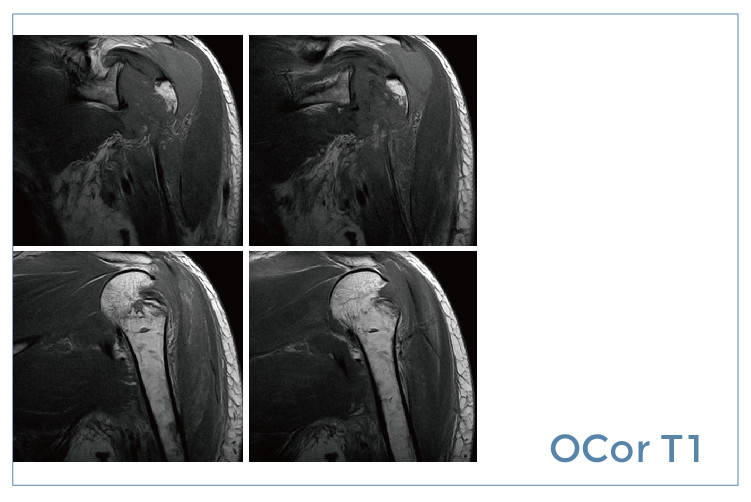

【朗润影像档案】磁共振影像病例分享(编号20190830)